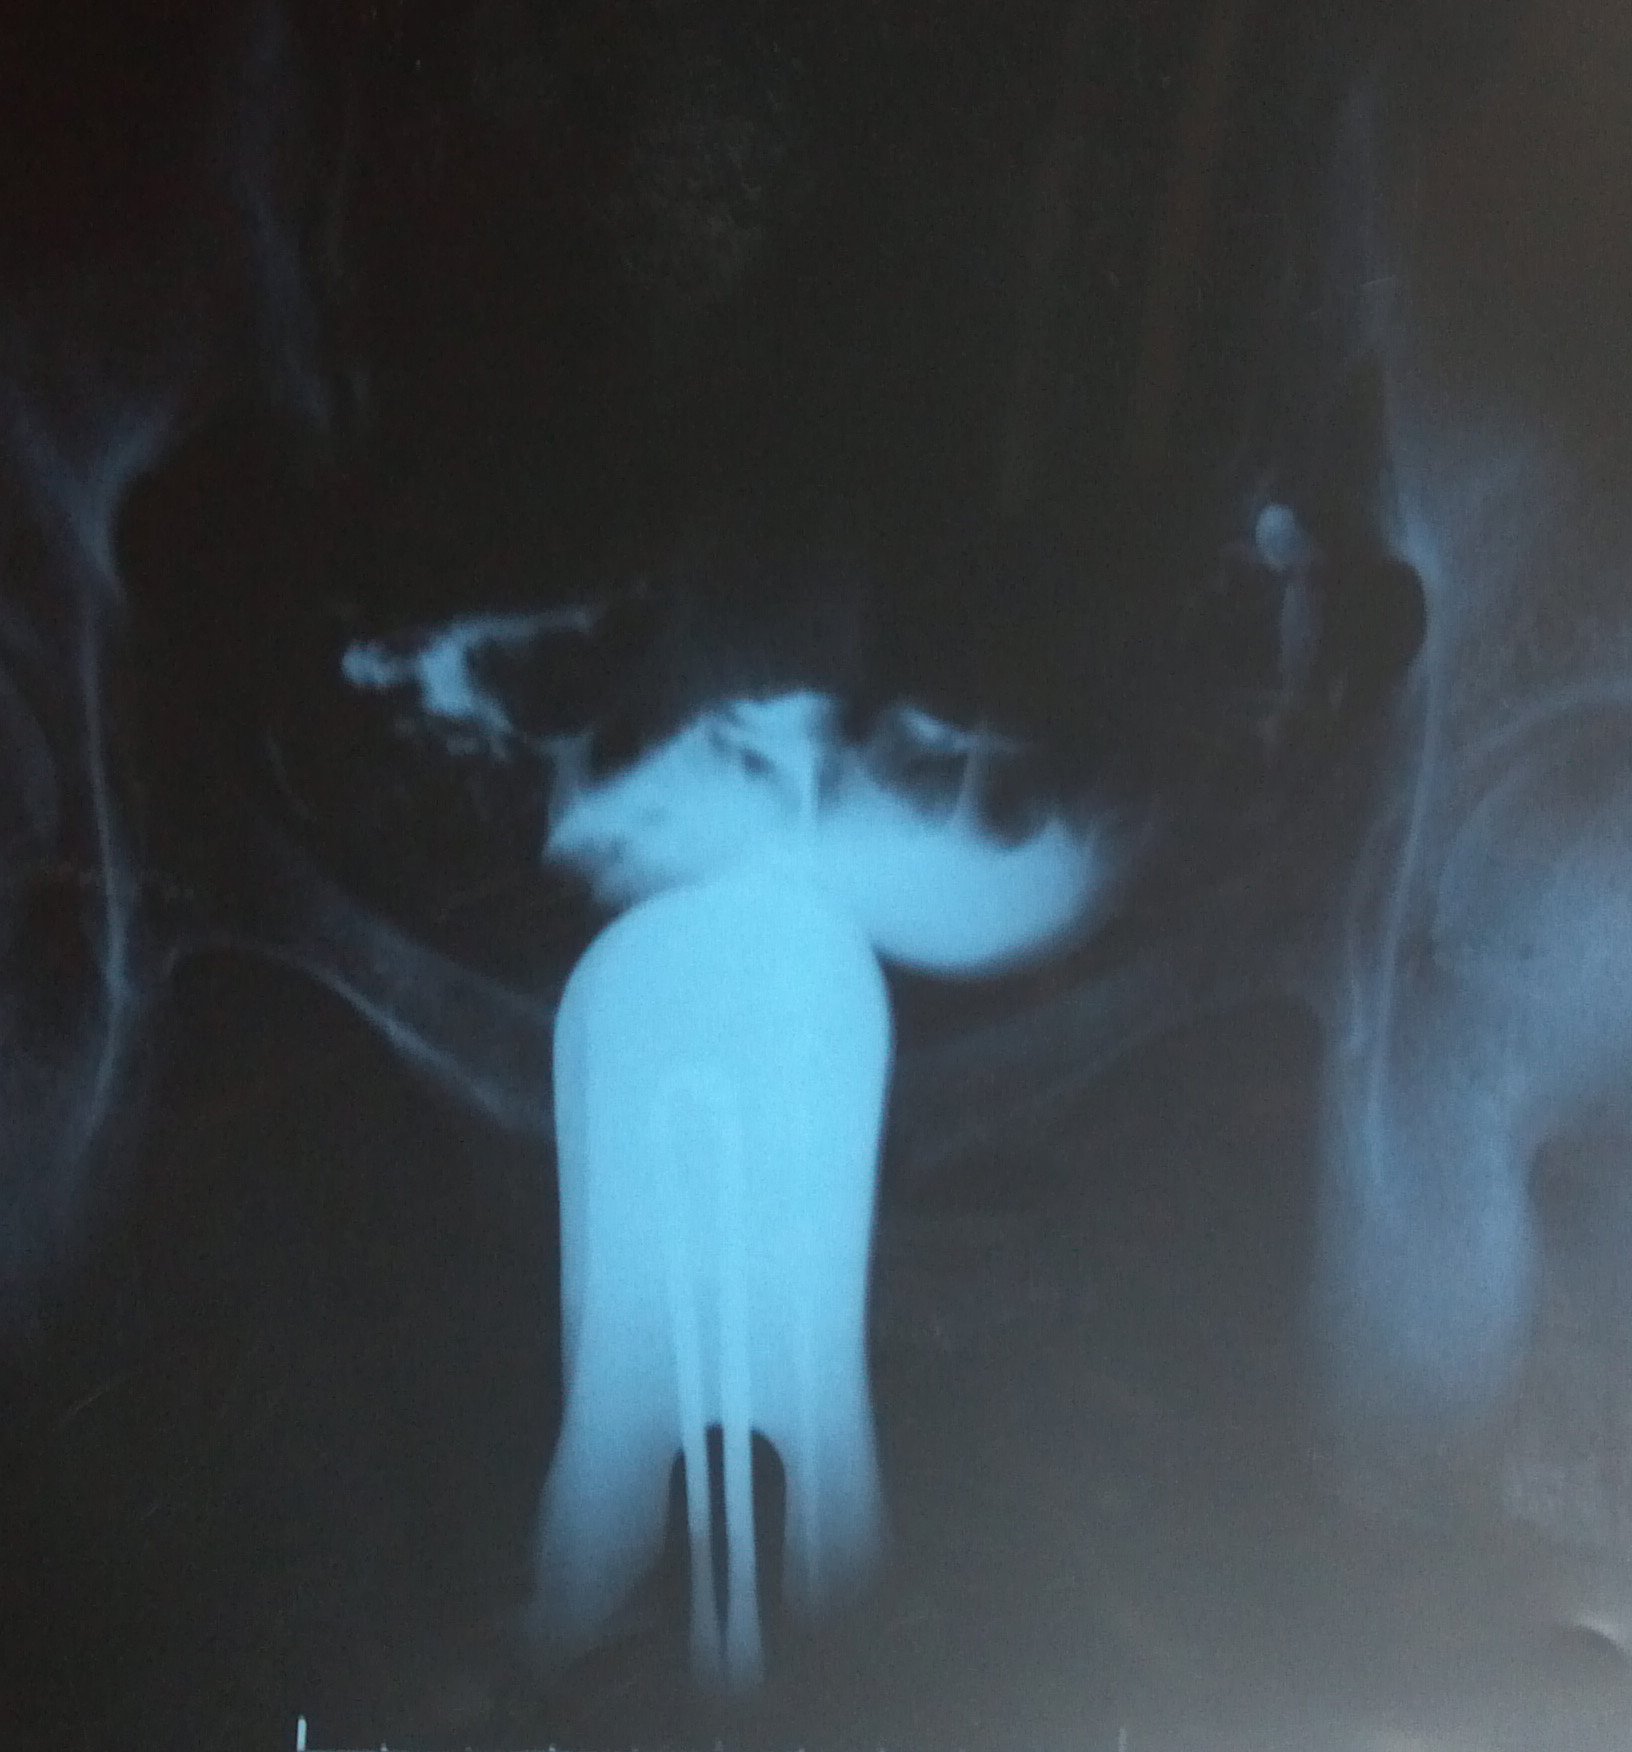

我去年8月做了造影 2年没有怀上小孩 以前做过人流,我想知道我的造影会影响怀孕吗?输卵管有粘连和积水? 点击展开 匿名用户 2013-03-05 13:53 为您推荐: 其他回答 你好, 你现在的情况需要进行保守治疗,由于你的是双侧的输卵管炎,用逐水舒管汤就可以了 匿名用户 2013-03-05 16:41 相关问题 我是去年9月做的人流,今年想怀孕,但是一直没有怀上,我需要做输卵管造影吗 怀孕九个多月了,现在查出小孩脑积水38,30小孩能要吗 09年开刀生过一个小孩 2011年怀孕 一次 当时不能要小孩 医生建议吃药人流没有感觉